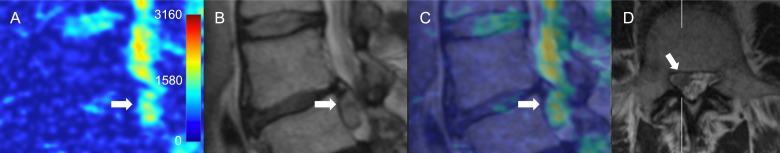

T1-weighted, T2-weighted and diffusion weighted (DWI) MR images of 100 consecutive patients admitted to the spinal surgery service were assessed. ADC maps were generated from DWI images using Osyrix software. The ADC values and characteristic ADC maps were assessed in the regions of interest over the different pathological entities of the lumbar spine.

The study included 452 lumbar vertebral segments available for analysis of ADCs. Characteristic ADC map features were identified for protrusion, extrusion and sequester types of lumbar disk herniations, spondylolisthesis, reactive Modic endplate changes, Pfirrmann grades of IVD degeneration, and compromised spinal nerves. Compromised nerve roots had significantly higher mean ADC values than adjacent (p < 0.001), contralateral (p < 0.001) or adjacent contralateral (p < 0.001) nerve roots. Compared to the normal bone marrow, Modic I changes showed higher ADC values (p = 0.01) and Modic 2 changes showed lower ADC values (p = 0.02) respectively. ADC values correlated with the Pfirrmann grading, however differed from herniated and non-herniated disks of the matched Pfirrmann 3 and 4 grades.

Quantitative and qualitative evaluation of ADC mapping may provide additional useful information regarding the fluid dynamics of the degenerated spine and may complement standard MRI imaging protocol for the comprehensive assessment of surgical patients with lumbar spine pathology. ADC maps were advantageous in differentiating reactive bone marrow changes, and more precise assessment of the disk degeneration state. ADC mapping of compressed nerve roots showed promise but requires further investigation on a larger cohort of patients.